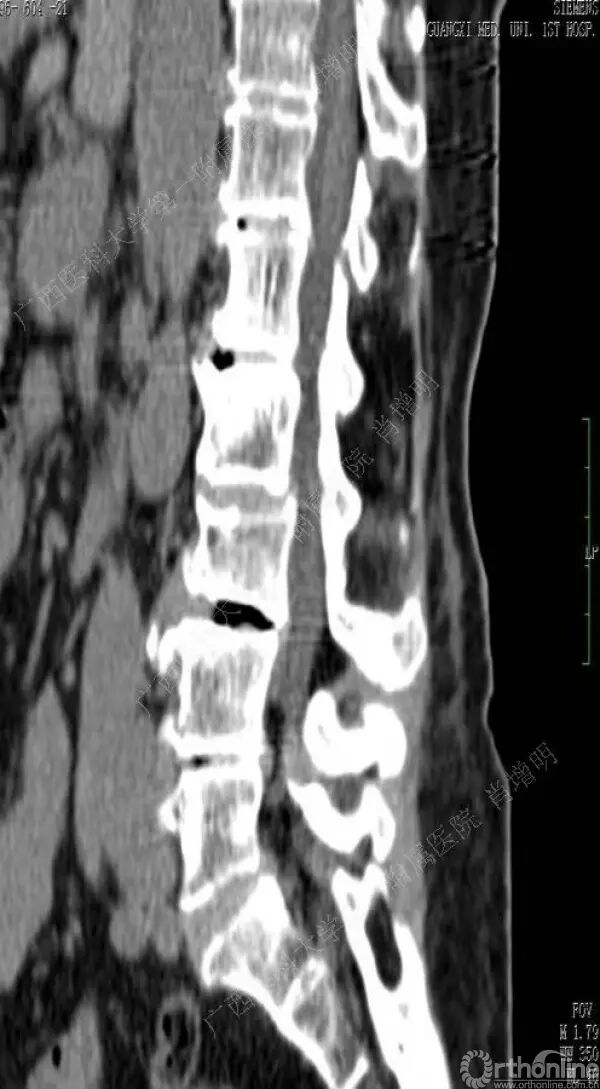

退变性脊柱侧凸是由于椎间盘退变后继发小关节退变,椎管和神经根管容积变化以及脊柱失稳,畸形等病理改变,以疼痛和神经压迫症状为主要表现的常见疾病。

退变性脊柱侧凸多发于50岁以上的中老年群体,是现代常见的老年疾病。多年来,针对该病的临床研究一直没有停步,广西医科大学第一附属医院肖增明教授细致地介绍了该病的诊疗进展。